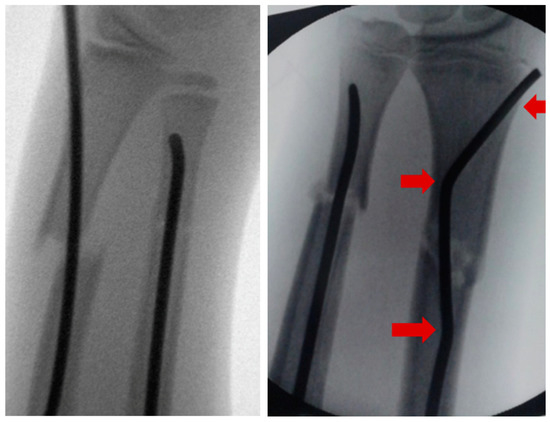

Intramedullary nails, however, if not pre-bent, usually lead to an unacceptable radial displacement of the distal fragment, which makes the situation sometimes worse than it was before (Figure 1). Pre-bending techniques have been described with a single kink, which is placed distal to the fracture, but these remain controversial due to lack of stability [3,10,11]. The same applies to unconventional techniques, such as locked wires [12].

The idea that this new surgical technique is based on is that, if a normal intramedullary nail being brought into the radius from the radial side of the distal radius, displaces the distal fragment radially, the solution would be to insert the nail from the ulnar side, which, however, is not possible, because this area cannot be accessed due to the close anatomical neighborship of the distal ulna. This makes it necessary to simulate an ulnar access. Therefore, the proximal (first) kink of the nail, which at the end of the procedure is placed proximal to the fracture, will push the radial corticalis of the proximal fragment radially, whereas the second kink (which can also be performed as a bend, see Scheme 1) pushes the distal fragment into an anatomical position and makes it possible for the nail to be brought into the distal radius using the established approach. If the entry into the bone is performed exactly with the diameter of the nail, stable osteosynthesis with three-point support is achieved (Figure 1).

After choosing the right diameter (which should not be as big as possible: about half the diameter of the intra-cortical space is ideal), the distance between skid and the proximal kink must be established. To avoid x-ray exposure to the surgeon’s hand, the nail is grasped with forceps and is placed on the patient’s arm, skid facing upwards. Under fluoroscopy, the position of the first kink is determined about 1 cm proximal to the fracture (skid must be distal to the growth plate of the proximal radius) and is marked by bending the nail slightly (the final bend of about 45° should be performed later: if it is performed now, the nail will not fit into the handpiece, see Figure 2). Now, a skin incision is performed, lateral of the distal radial growth plate, and the radial metaphysis is perforated, just proximal to the growth plate, as in ‘normal’ intramedullary nailing. The nail is introduced into the bone until the kink appears between the bone and handpiece: now the kink is completed to at least 45°. This is the important moment; the second kink must be performed, about 2–3 cm distal to the first kink (the distance between the kinks equals about twice the diameter of the radius in the region of the fracture), in the opposite direction to the first kink, again at least 45° (Figure 2). The nail can be bent to modify the distal kink (Scheme 1); however, the aim is that this kink finally gets contact to the ulnar-sided cortical of the radius and leads to a tension-free curve to the area of insertion.

Figure 1. Intramedullary nailing without pre-bending of the radial nail leading to a radial displacement of the distal fragment whereas double pre-bent nail ensures three-point support.